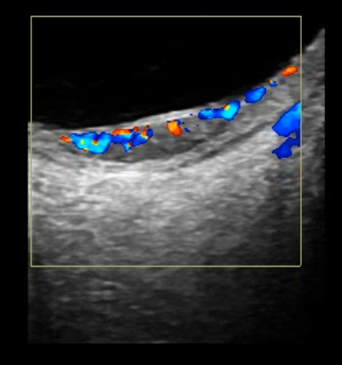

L’Écho-Doppler est une technique d’imagerie échographique permettant d’observer les flux sanguins au sein des vaisseaux intra-oculaires et orbitaires.

Il est principalement indiqué pour rechercher une vascularisation anormale au niveau de la rétine, du nerf optique ou de l’orbite.

L’examen peut également mettre en évidence la présence d’un flux sanguin dans une tumeur oculaire, ce qui aide à orienter le diagnostic sur la nature de cette lésion.

Deux modes sont utilisés : l’Écho-Doppler couleur et le Doppler énergie.

Le Doppler énergie est particulièrement utile pour détecter des vaisseaux de très petit calibre et est moins sensible à l’angle du flux sanguin.